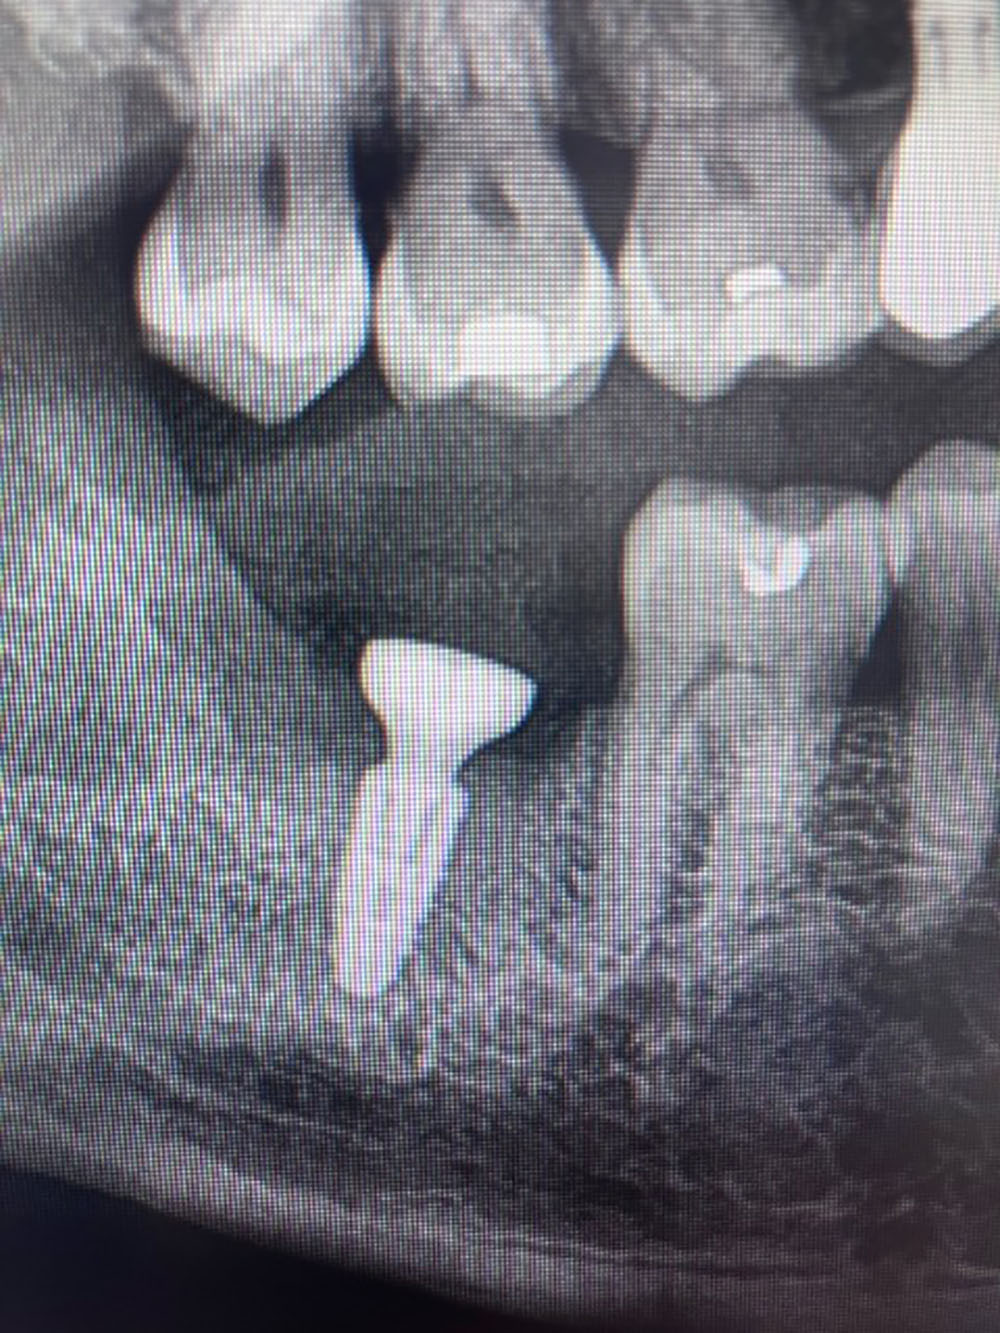

Patient de 65 ans sans pathologie générale présentant une dent de sagesse incluse et la nécessité de remplacer une dent adjacente par un implant. Le volume osseux était insuffisant sans adaptation.

Analyse CBCT : dent de sagesse incluse avec potentiel osseux exploitable, zone implantaire nécessitant une greffe, anatomie compatible avec une chirurgie combinée.

Implant bien positionné avec bon comblement osseux et respect des structures anatomiques.